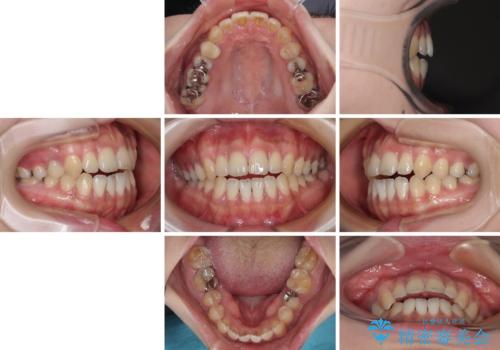

開咬をワイヤー装置で矯正治療

- 上下前歯が非接触となっている咬み合わせを気にして来院された患者様です。

開咬となっている原因の大半は、舌の突出癖によるものであるため、治療開始前から舌のトレーニングを開始し、スムーズに治療が進むようにしました。

開咬の方は、インビザライン矯正治療が適していますが、自己管理の煩わしさと、転勤の可能性がありマウスピース矯正であると通院しなくなるだろうとのことで、ワイヤー装置にて矯正治療を行うこととしました。